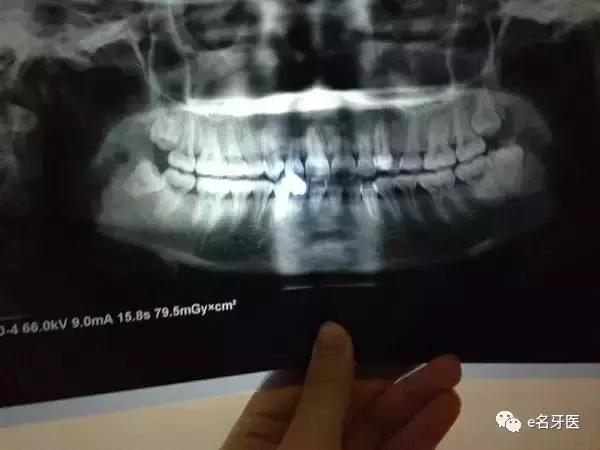

因为她不仅小*牙虎**长得过于突出了,

还有些许的牙列拥挤,中线不齐,

牙齿歪歪扭扭的很容易滋生细菌的你滋不滋道。

▲这就是牙齿模型,一点都不恐怖对不对

医生的治疗建议是:

上下各拔一颗,调整好牙中线和*牙虎**的位置。